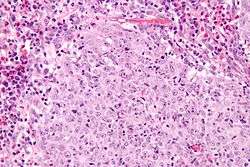

| Micrograph of a glassy cell carcinoma of the cervix. H&E stain. | |

Glassy cell carcinoma of the cervix, also glassy cell carcinoma, is a rare aggressive malignant tumour of the uterine cervix.[1] The tumour gets its name from its microscopic appearance; its cytoplasm has a glass-like appearance.

Under the microscope, glassy cell carcinoma tumours are composed of cells with a glass-like cytoplasm, typically associated with an inflammatory infiltrate abundant in eosinophils and very mitotically active. PAS staining distinctively extenuates the plasma membrane.[2]